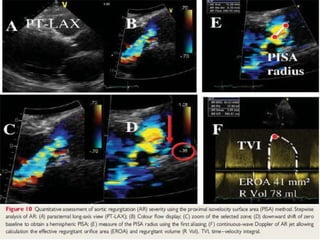

PISA

• Technically not possible to visualize the isovelocity shells that

converge on the AR orifice.

Area =2r2

Flow= Area * Va

EROA = FLOW/V max

RV= ERO* VTI

Volumetric method

• The four valves in the heart are in series,the flow or stroke

volume at any point must be equal.

• In AR,the total stroke volume through the aortic valve in systole

must equal the forward stroke volume(other nonregurgitant

valve) plus the regurgitant volume.

• Stroke volume = product of CSA x TVI.

• Forward stroke volume at mitral vlave ( in competent)

• Total stroke volume at aortic valve – forward + regurgitant.

• Regurgitant volume = aortic – mitral.

• Validated.

• Regurgitant fraction = RV/SV *100

Regurgitant volume = AV stroke volume –MV

stroke volume

• Regurgitant volume greater than 60 ml indicates severe AR.

• Regurgitant fraction greater than 50%